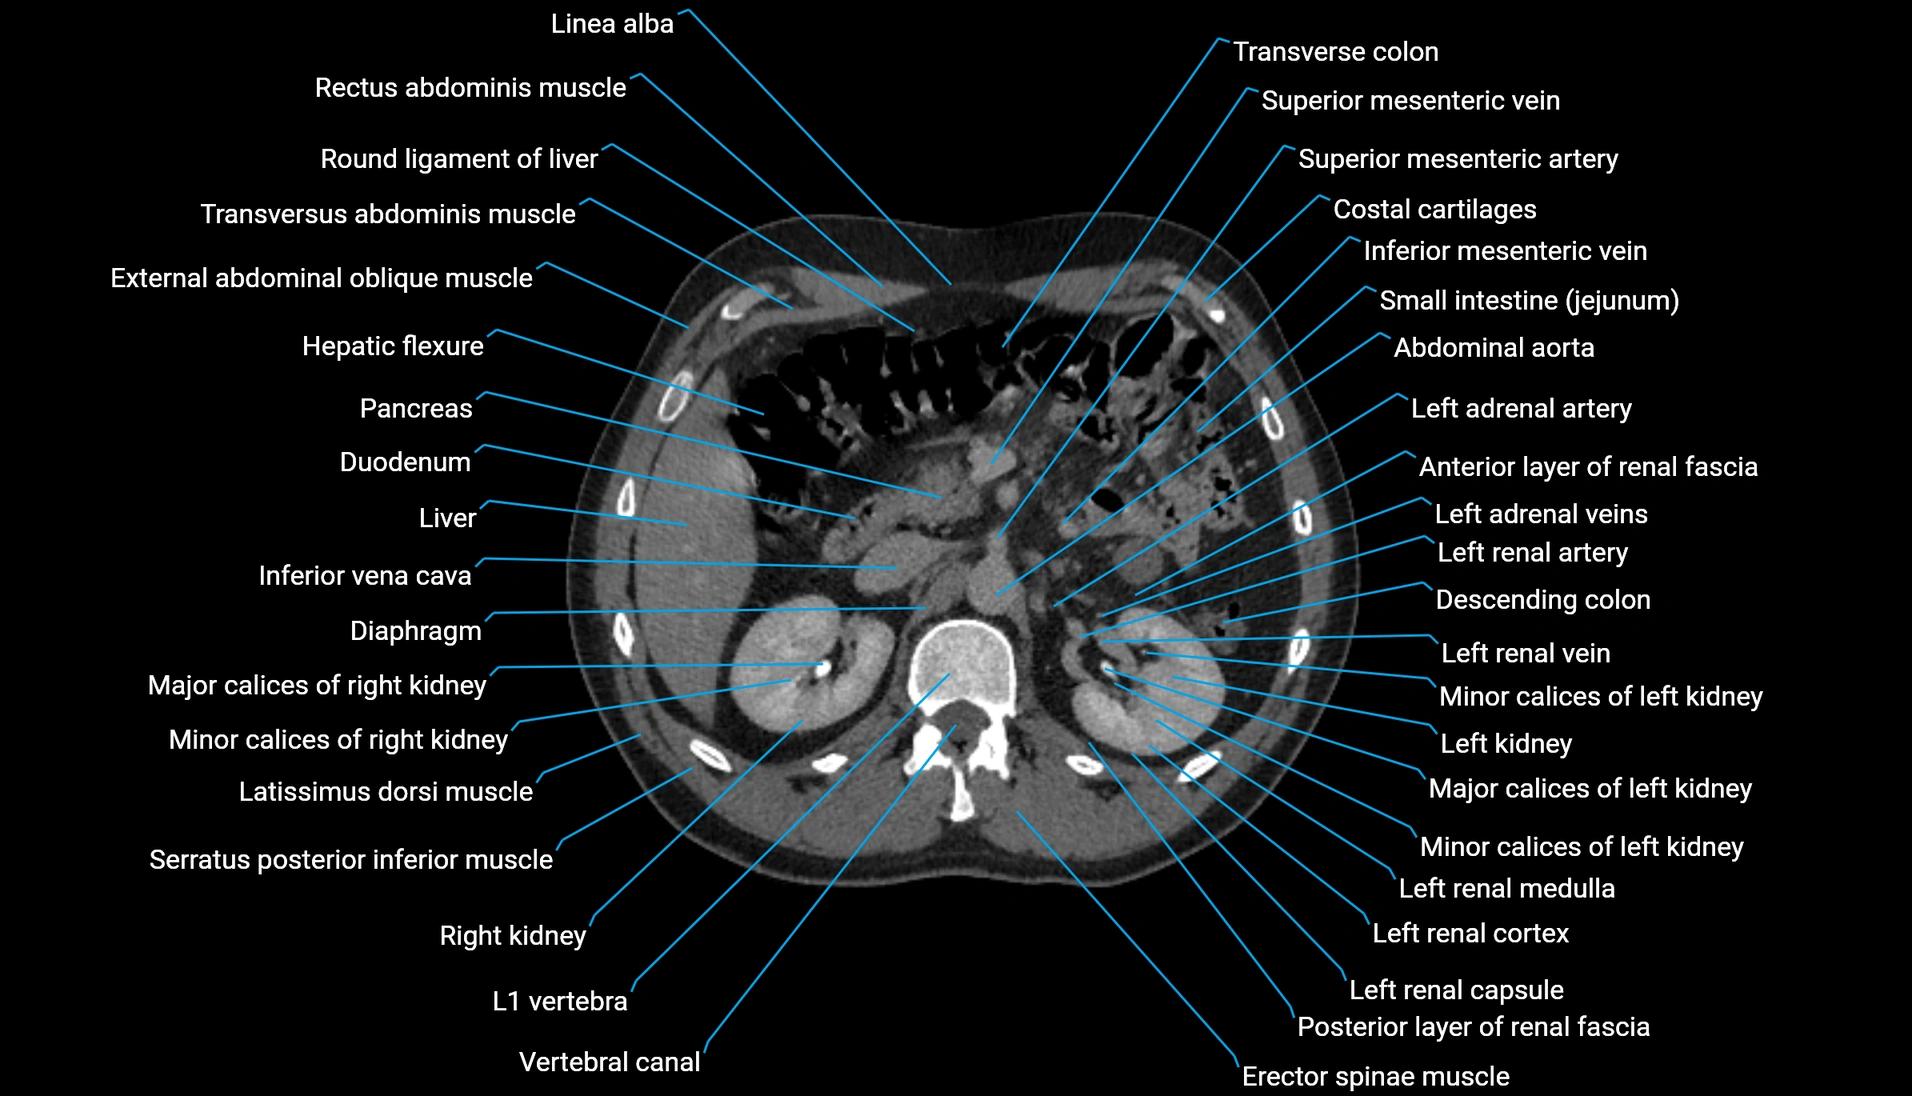

CT Appearance

Non-contrast CT:

-

Demonstrates cortical bone of acetabular rim in excellent detail

Detects fractures, dysplasia, retroversion, or bony overcoverage (pincer impingement)

3D reconstructions used in preoperative hip surgery planning

CT VRT 3D image

CT image